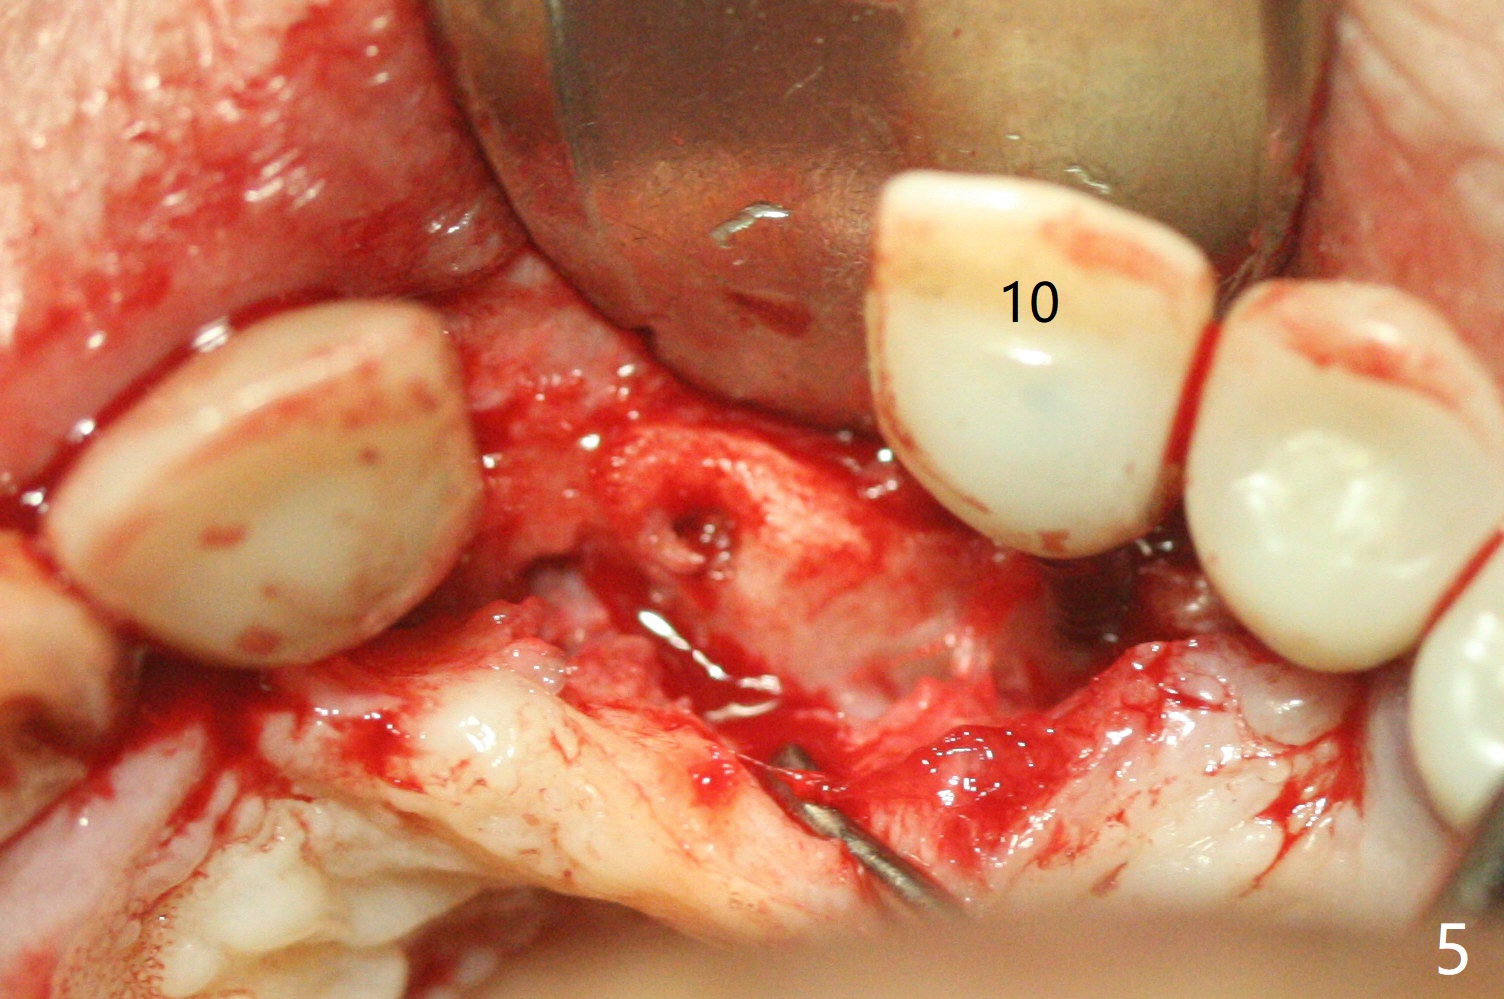

The implant access at #9 closes 1 week post implant fracture (Fig.1,4). There is mild gingival erythema at #10 (Fig.2,3 ^). There is bone around the fractured implant, which is palatally placed (Fig.5). The 2 mm implant is removed using 2/3 mm trephine bur. In spite of moving the osteotomy buccally, a 4.5x4 mm, 15 degree A-type angled abutment is installed for an immediate provisional following placement of a 3.5x10 mm implant (Fig.7, 25 Ncm). Sticky bone is placed (Fig.7 *) palatal to the implants at #9 and 10 (with thread exposure, Fig.6). While the majority of periodontal dressing remains in place (Fig.9,10), the suture in the exposed area appears to hold the papilla in place (Fig.8 <). Herpetic infection develops in the palate (Fig.9). Two months later, the gingiva at #10 is healthy; it appears that the implant threads are covered by bone graft. The immediate provisional (fabricated before suture) keeps the gingiva in an ideal position for impression of final restoration. It appears that the access hole is in a right area for screw retained restoration. The gingival cuff is healthy immediate pre-cementation, 4 months postop (Fig.12,13). The lab does not make access hole for the final crown (Fig.14). The implant remains subcrestal 4 months postop (Fig.15). Since the shade of the crown is off, the abutment remains un-torqued and the crown is cemented with temp bond. The implant threads at #10 seem to be covered by bone graft 4 months postop (Fig.16).